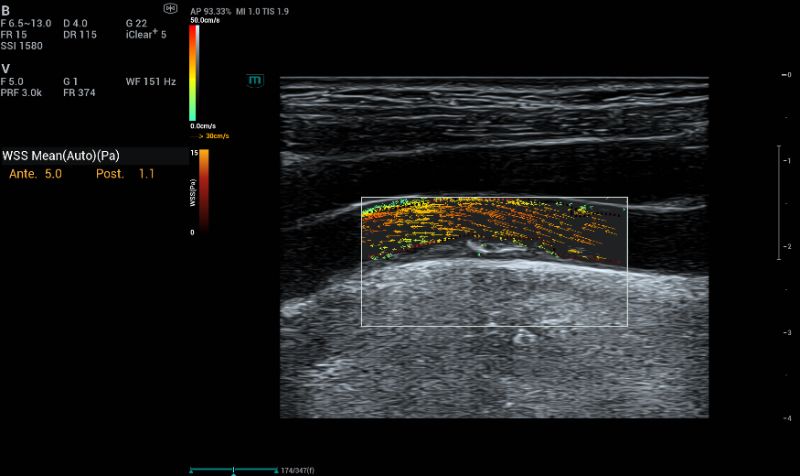

V Flow can quantify a new ultrasound parameter defined as “wall shear stress” (WSS), representing the friction force exerted by the blood flow on each point of the endothelial atheroma surface. Considering that a plaque is strongly affected by hemodynamic changes due to shear stress, WSS could became a determining factor in assessing plaque evolution and stratifying patient risk, even for asymptomatic patients.

Low WSS (<0.4 Pa) may influence the morphology and function of endothelial cells, closely associated with intimal thickening and the formation of atherosclerosis. High WSS values (>7Pa) for an atherosclerotic surface are potentially indicative of plaque vulnerability and so could be predictive of future complications related to thromboembolic events. At the upstream sides of carotid stenosis, plaque with a lower mean WSS was associated with decreased fibrous tissue. At the peak of carotid stenosis, meanWSS was higher in the plaques with intraplaque hemorrhage and intraplaque neovascularization. High WSS is generally linked to plaque rupture, while low WSS facilitates plaque development.

Auto WSS were measured at the stenosis providing valuable parameter for plaque evaluation.

Fig.8: Auto WSS were measured at the stenosis providing valuable parameter for plaque evaluation.